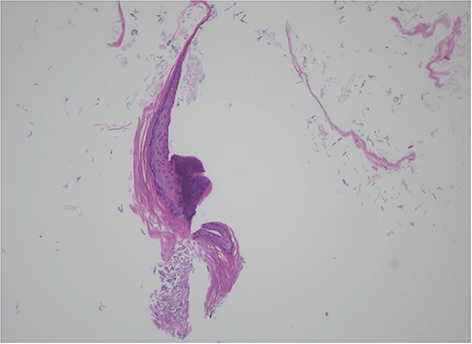

A 32 month-old girl was referred by a pediatrician to a pediatric surgeon in our hospital on account of an abscess-like lesion of the left nipple, which has existed since birth and was similar to ‘witch's milk’. She was born by normal vaginal delivery at gestational age 40 weeks, with a birth weight of 3800g. There had been no traumatic or surgical event on the left nipple in her medical history. The initial finding was a milk-colored tense nontender pustule, which covered the whole surface of the nipple. Ultrasonography showed a 6×5 mm round cyst with no specific connection to the underlying breast. Thus, on the impression of congenital milium of the nipple, incisional evacuation, which squeezes out of inner contents of the mass after incision with the tip of a 23-gauge needle was performed in the outpatient clinic, and the wound remained open (

Fig. 1 The congenital milium of the nipple. (A) Gross finding of patient at the first visit. (B) Ultrasonography finding. (C) First operative procedure: incisional evacuation by needle.